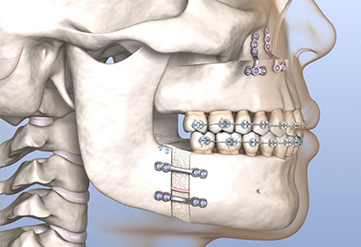

Surgical orthodontics, also known as orthognathic surgery, combines orthodontic treatment wih jaw surgery to correct severe jaw and bite misalignments, inproving both function and aesthetics.